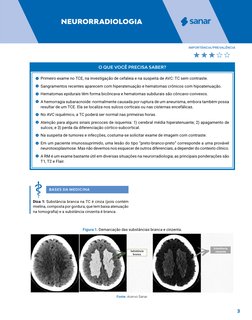

BASES DA MEDICINA

Dica 1: Substância branca na TC é cinza (pois contém

mielina, composta por gordura, que tem baixa atenuação

na tomografia) e a substância cinzenta é branca.

Figura 1. Demarcação das substâncias branca e cinzenta.

Fonte: Acervo Sanar.

Dica 2: Principais marcos anatômicos.

Figura 2. Marcos anatômicos.